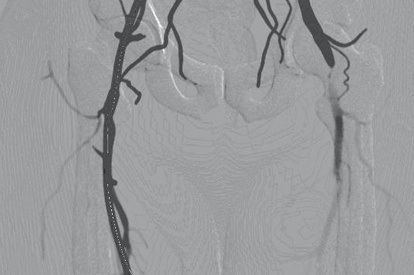

The ANGIO Mentor simulator is an essential tool for clinicians to practice and acquire the skills needed for performing endovascular interventions. Trusted by medical associations, hospitals, training centers, and the medical device industry globally, it provides trainees with realistic clinical settings to practice endovascular interventions using fluoroscopic and ultrasound guidance.

With a library of over 35 modules, growing with the evolution of endovascular techniques and devices, the simulator caters to 11+ medical specialties and offers training from basic skills to advanced interventions.

EVAR (Endovascular Aneurysm Repair) Module